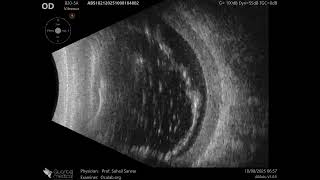

20 MHz Annular Ophthalmic Ultrasound ABSolu, Subhyaloid hemorrhage , 36660